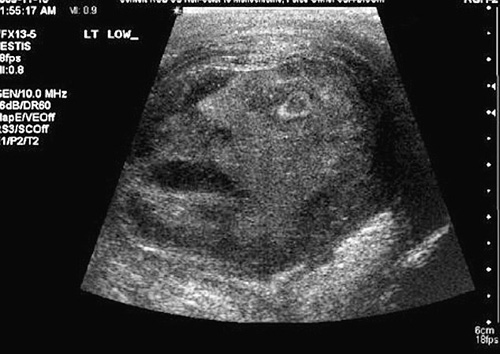

Mặt người kỳ lạ xuất hiện khi siêu âm khối u tinh hoàn một bệnh nhân ở Canada.

Bác sĩ G. Gregory Roberts và Naji J. Touma đến từ Đại học Queen ở Ontario, Canada trong lúc thực hiện loạt siêu âm để kiểm tra những bất thường ở tinh hoàn của một bệnh nhân 45 tuổi đã phát hiện hình ảnh mặt người kỳ lạ tại đó. Sự việc này hai vị bác sĩ cảm thấy vô cùng sửng sốt.

Hình ảnh trên máy quét siêu âm cho thấy một khuôn mặt có vẻ "đau khổ" với chiếc miệng há hốc đã xuất hiện trong khối u tinh hoàn của bệnh nhân. Hai bác sĩ G. Gregory Roberts và Naji J. Touma rất ngạc nhiên và họ đã gửi hình ảnh này lên Urology - tạp chí chính thức của Hiệp hội quốc tế về tiết niệu học.

Mặt người kỳ lạ xuất hiện khi siêu âm khối u tinh hoàn một bệnh nhân ở Canada |

Hai vị bác sĩ cho biết: "Chúng tôi và các nhân viên y tế đều hết sức sửng sốt khi thấy khuôn mặt của người đàn ông trong bức ảnh siêu âm. Khuôn mặt đó trông rất... đau khổ, như thể "anh ta" cũng có khối u tinh hoàn vậy."

Sau khi tình huống bất ngờ này xảy ra, những luồng ý kiến trái ngược đã nổ ra. Nhiều người cho rằng, đây là dấu hiệu của một vị thần nhưng đa số đều nhất trí rằng khuôn mặt đó chỉ là một sự trùng hợp ngẫu nhiên. Các bác sĩ đã cắt bỏ khối u tinh hoàn của bệnh nhân. Thật may mắn cho người đàn ông này vì đó chỉ là một khối u lành.